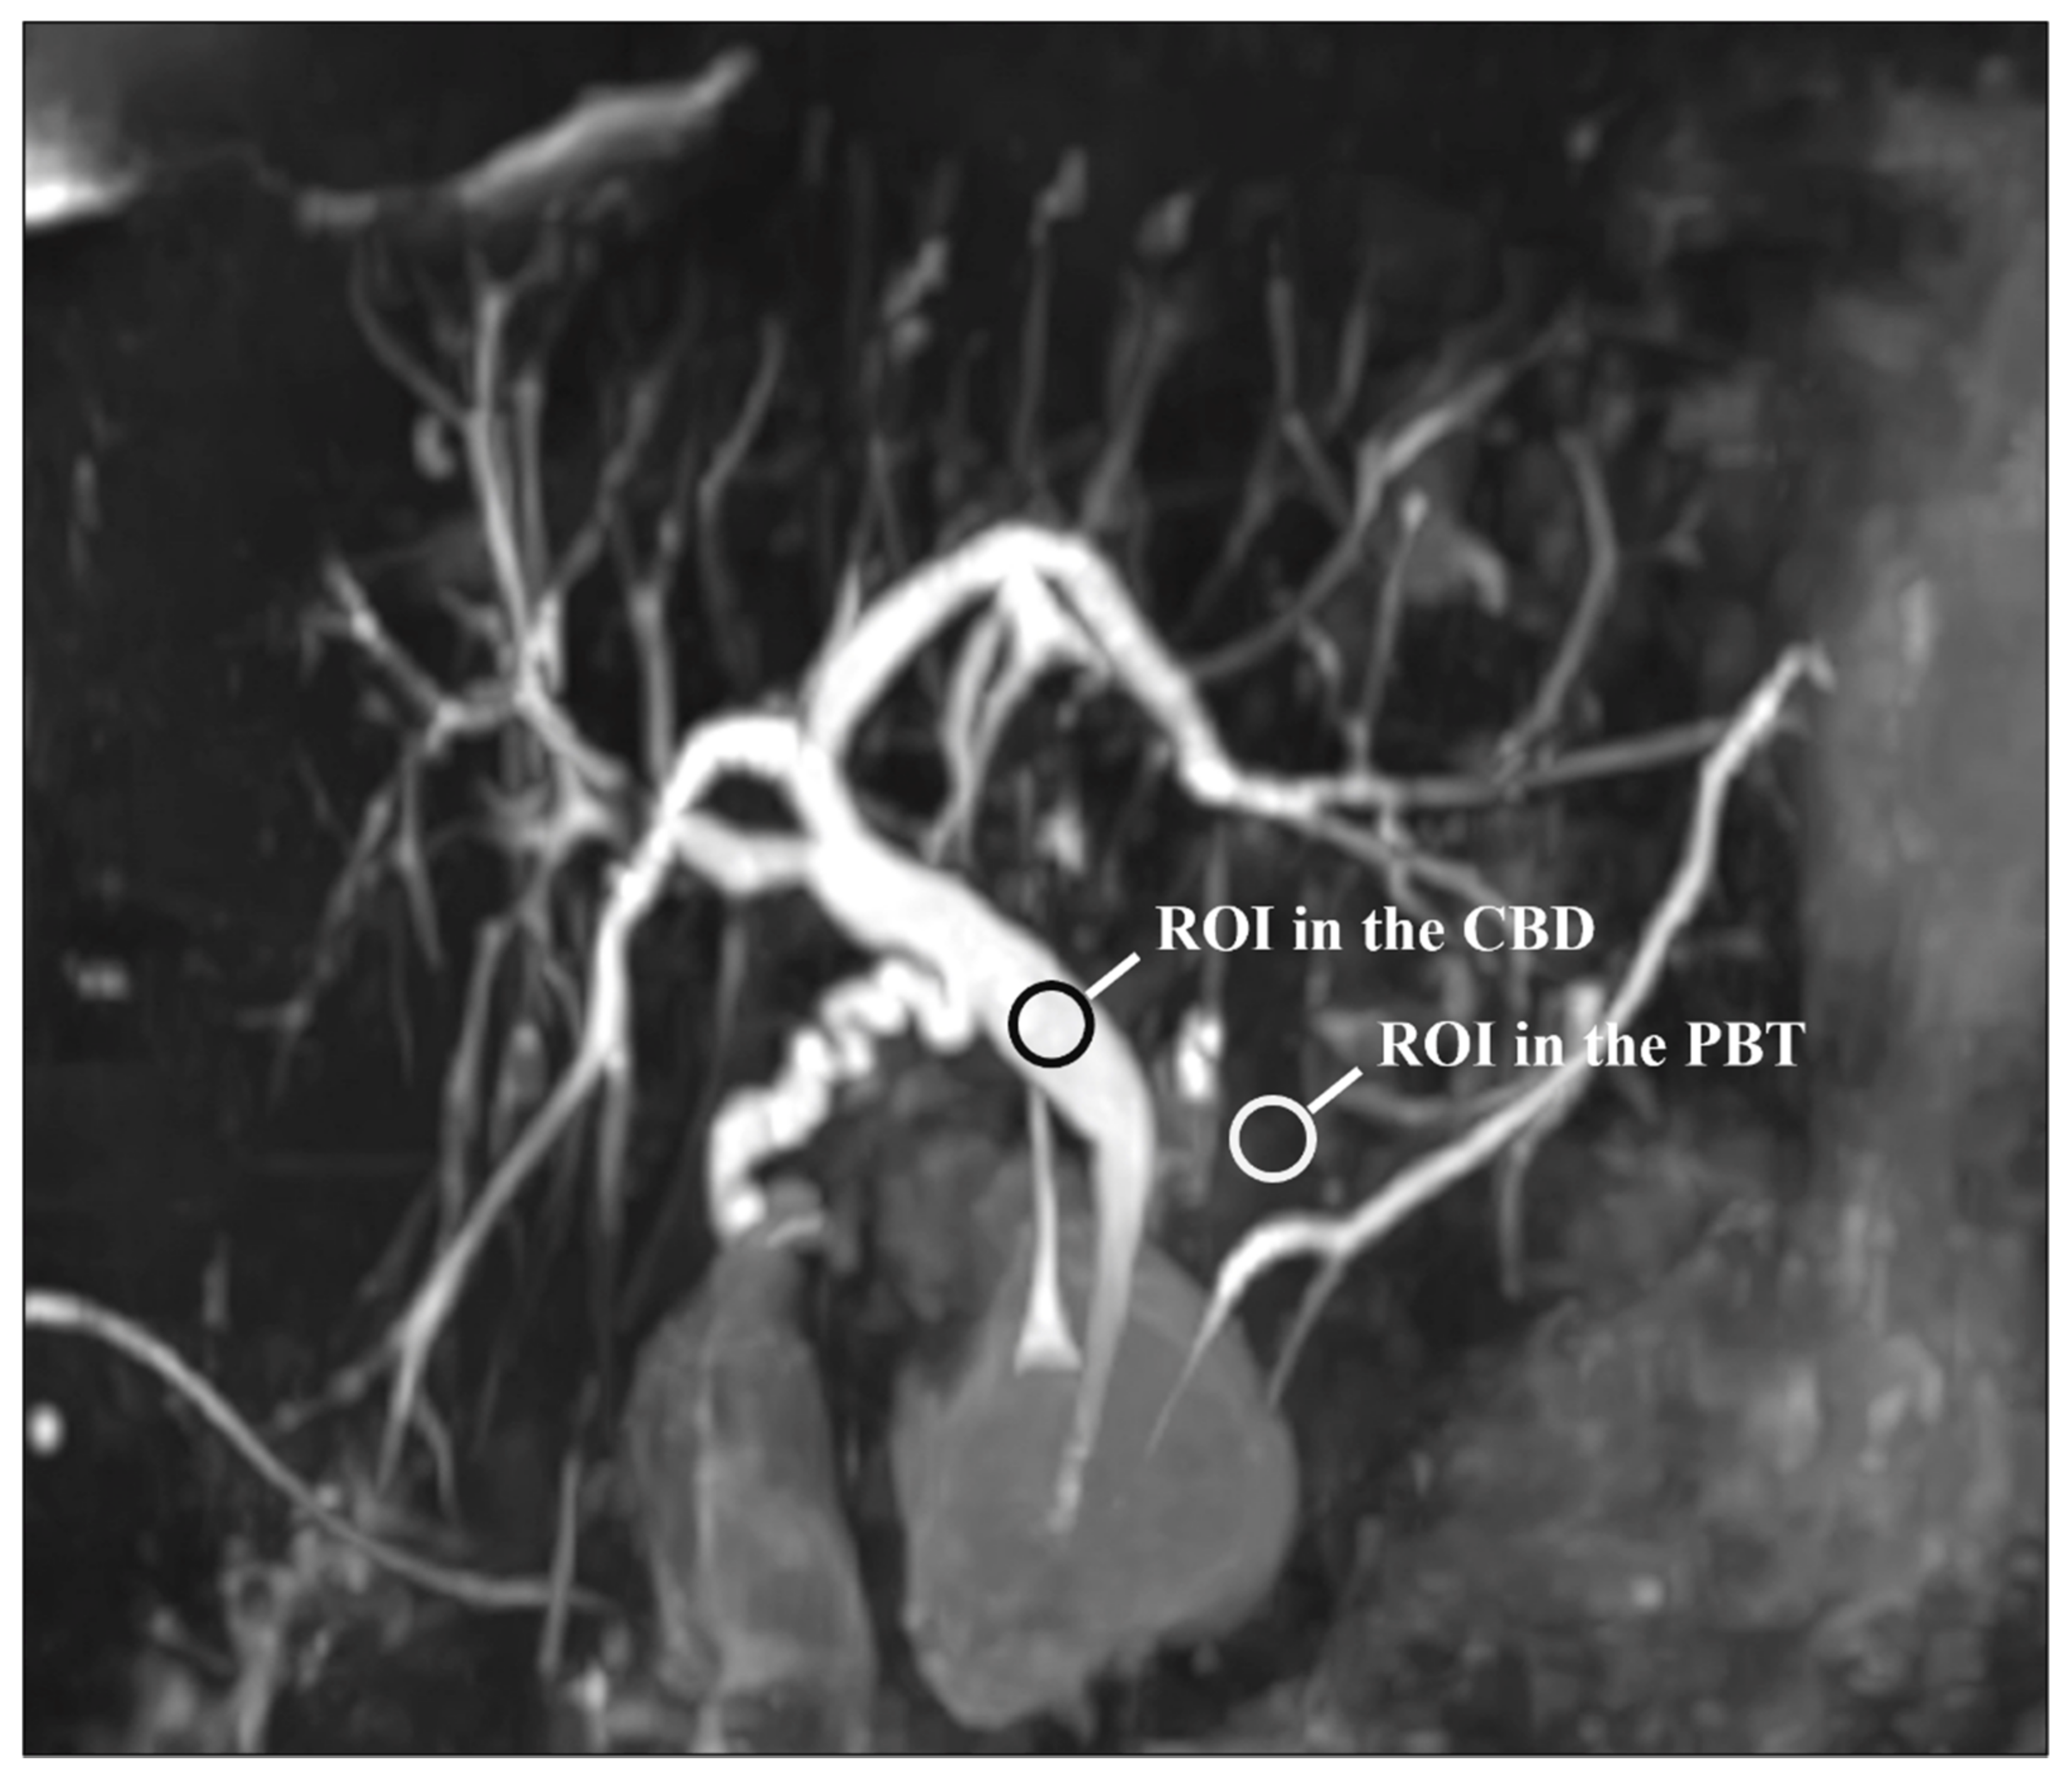

For each patient and each sequence, a representative section of the CBD was selected. Then, circular regions of interest (ROIs) were traced on the CBD and PBT and the mean signal intensities were recorded. The CBD ROI was at least 5 mm² and was placed in a uniform artifact-free region in the middle of the duct. A similar ROI was positioned on the peri-CBD tissues, avoiding artifacts and fluid-containing structures. Note that the ROIs were drawn on the native images. Figure 1 shows the ROIs placement. The CR was estimated using the following formula [23,29,30]:

Figure 1.

Representative section of the common bile duct (CBD) used for the quantitative evaluation of image quality: note the regions of interest (ROIs) on the CBD and peri-biliary tissues (PBT). Note that the ROIs were drawn on the native images and not on the MIP reconstruction as shown here.